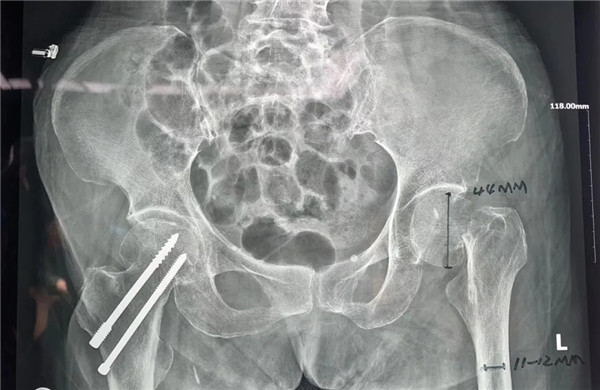

家人趕快第一時(shí)間將她送至我院,經(jīng)拍片后診斷為:左髖股骨頸頭下型骨折,病人入住關(guān)節(jié)科病區(qū)。

確定手術(shù)后,經(jīng)內(nèi)科、麻醉科、超聲科等專家會(huì)診后,王老太太符合手術(shù)指征,3月5日,老太太接受了股骨頭置換手術(shù)。